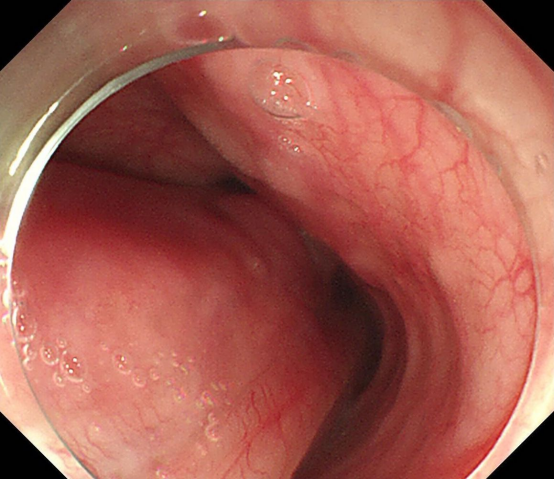

经过和患者及家属详细沟通后,胡兵教授团队制定了详细的手术方案,2025年1月15日,手术正式进行。在内镜引导下,胡兵教授利用高频电刀先切开病变基底部周边黏膜,进入黏膜下层,再逐步剥离病变基底部。由于病变太大,通过常规内镜下圈套器套住病变取出的方法力量太小,难以将病变全部取出,胡兵教授巧妙应用了外科手术中使用的卵圆钳将已经拖出体外的病变部分夹住后将全部病变顺利取出。40分钟后,胡兵教授完整切除了巨大包块,且术中出血量少(图1、图2、图3)。术后病变测量大小约22.0*5.5cm(图4)。病理检查显示为巨大纤维血管息肉。

(图2)